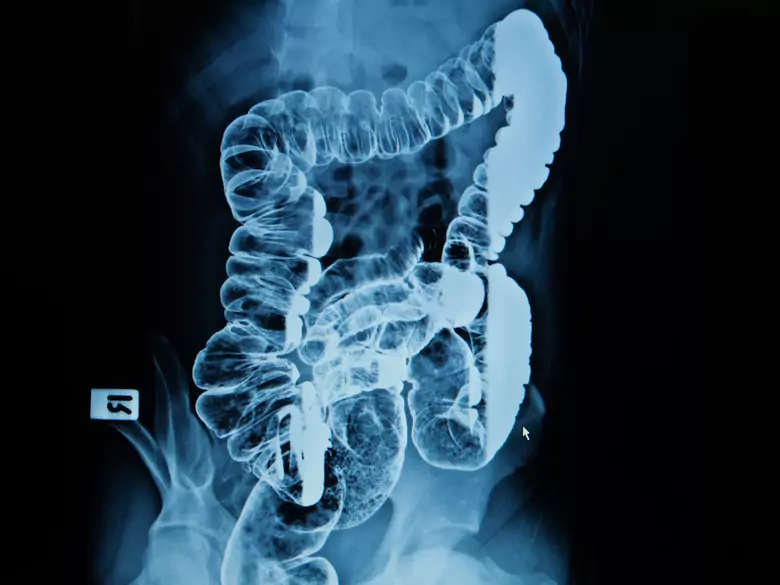

Jelita

Najnowsze badania naukowe pokazują, że witamina C posiada ogromne zastosowanie w medycynie. Jej wpływ jest bardzo korzystny dla naszego zdrowia.